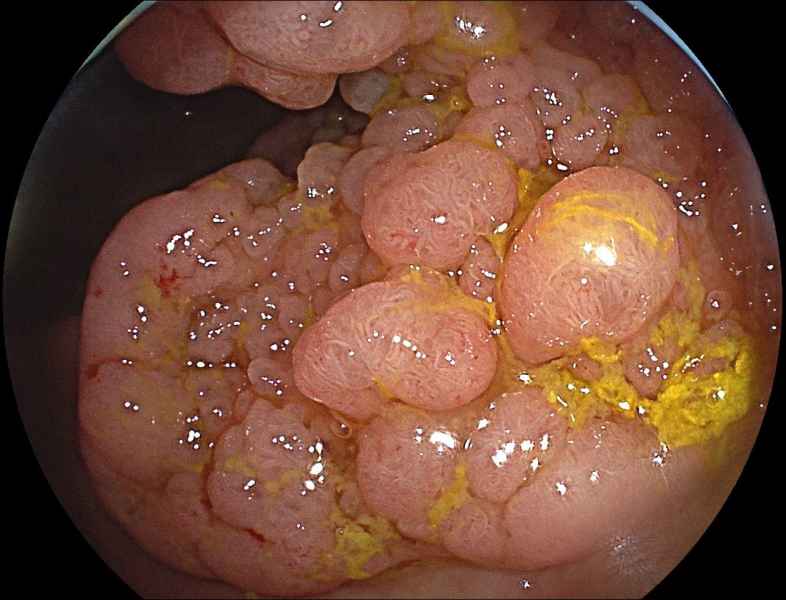

A Sea of polyps

Fotografia